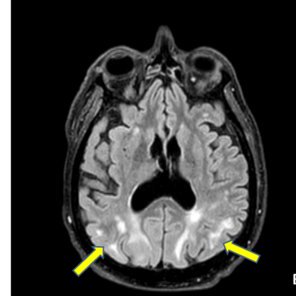

A rare cause of PRES secondary to EPO analogue. Our case report https://t.co/BfjiqvYsQW

cureus.com

Posterior reversible encephalopathy syndrome (PRES) is a potentially life-threatening but reversible neurological disorder. Commonly seen in the intensive care unit (ICU), PRES can arise from un...